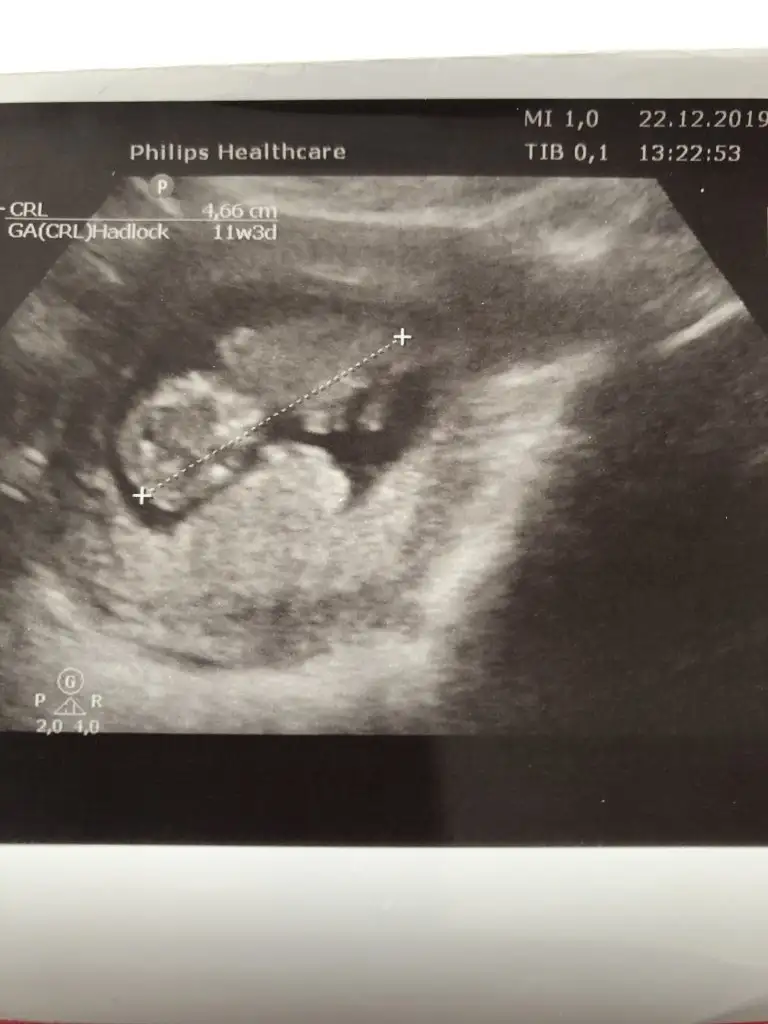

Slm güzel anneler bizde 11+1haftalik olduk bizede bir tahmin edermisiniz

birde bu şekilde var canımNet degil gördüğüm diklik nub ise erkek gibi ama eminde değilim başka usg varmı 11 yada 12 hafta